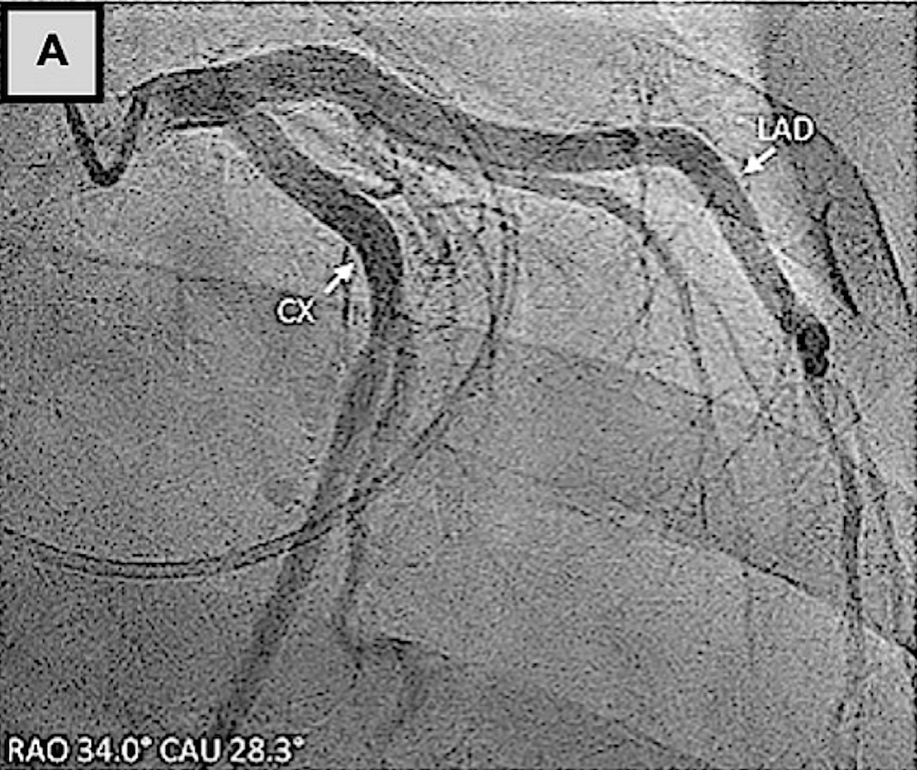

Amplatze左心耳封堵术与左冠状动脉的关系

(A)使用Amplatzer装置的左心耳封堵术已完全展开。冠状动脉造影证实,在植入后,回旋支-M1冠状动脉存在明显狭窄。(B)回旋支-经皮冠状动脉介入治疗

临床病例报告也证实了该损伤的可干预性:一例59岁患者行Amulet装置左心耳封堵时,因装置压迫导致LCX近端重度狭窄,出现下壁ST段抬高,重新将装置深入左心耳开口并联合LCX-PCI后,狭窄完全解除;另一例患者行二尖瓣、三尖瓣手术联合AtriClip装置左心耳封堵后24小时,因装置压迫导致LCX闭塞引发心肌梗死,经LCX-PCI后狭窄显著改善。

因此,外科操作中需将AtriClip装置放置于远离左心耳基底部的位置,避免LCX闭塞。